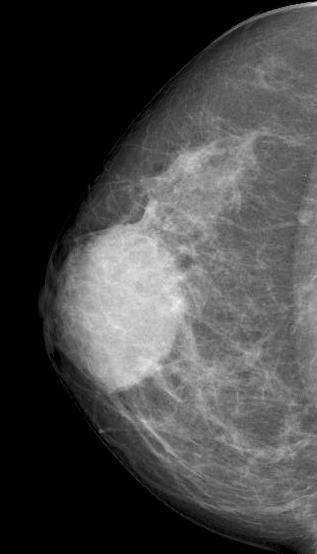

October 2020

A 49-year old asymptomatic female underwent routine screening mammogra...

Read More